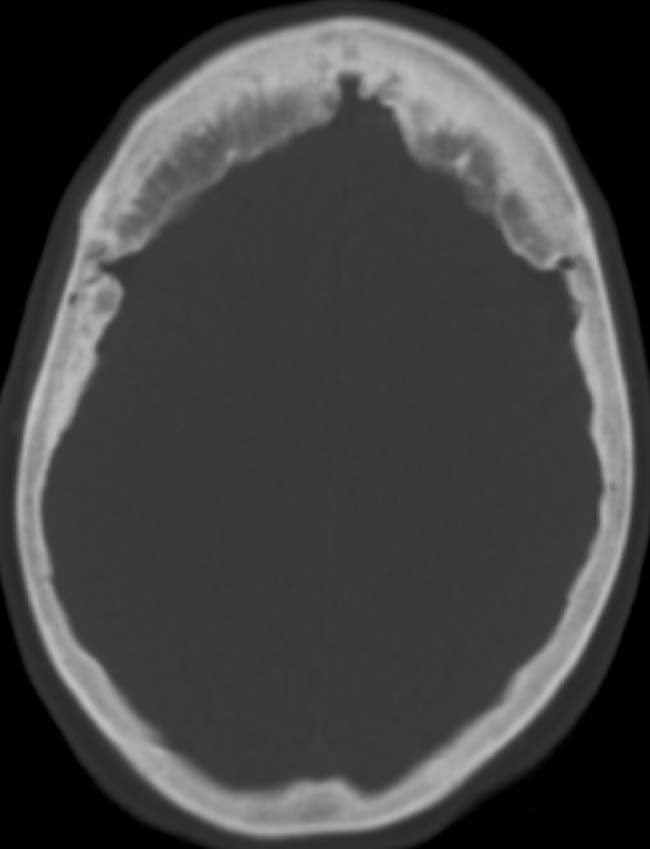

При фронтальном гиперостозе проводится рентгенографическое обследование черепа. В норме внутренняя пластинка лобной кости на рентгенограммах черепа имеет достаточно ровный и чёткий контур. В случае синдрома Морганьи-Мореля-Стюарда в этой зоне наблюдаются утолщения и костные разрастания.

Диагноз фронтальный гиперостоз выставляют на основании характерных симптомов и данных рентгенографии черепа. На рентгенограммах выявляются костные разрастания в области лобной кости и турецкого седла.

Внутренняя пластинка лобной кости утолщена. При проведении рентгенографии позвоночника нередко тоже обнаруживаются костные разрастания. При исследовании уровня гормонов в крови больных гиперостозом определяется повышенное количество гормонов коры надпочечников, адренокортикотропина и соматостатина.

КТ головного мозга. Гиперостоз внутренней замыкательной пластинки лобной кости.